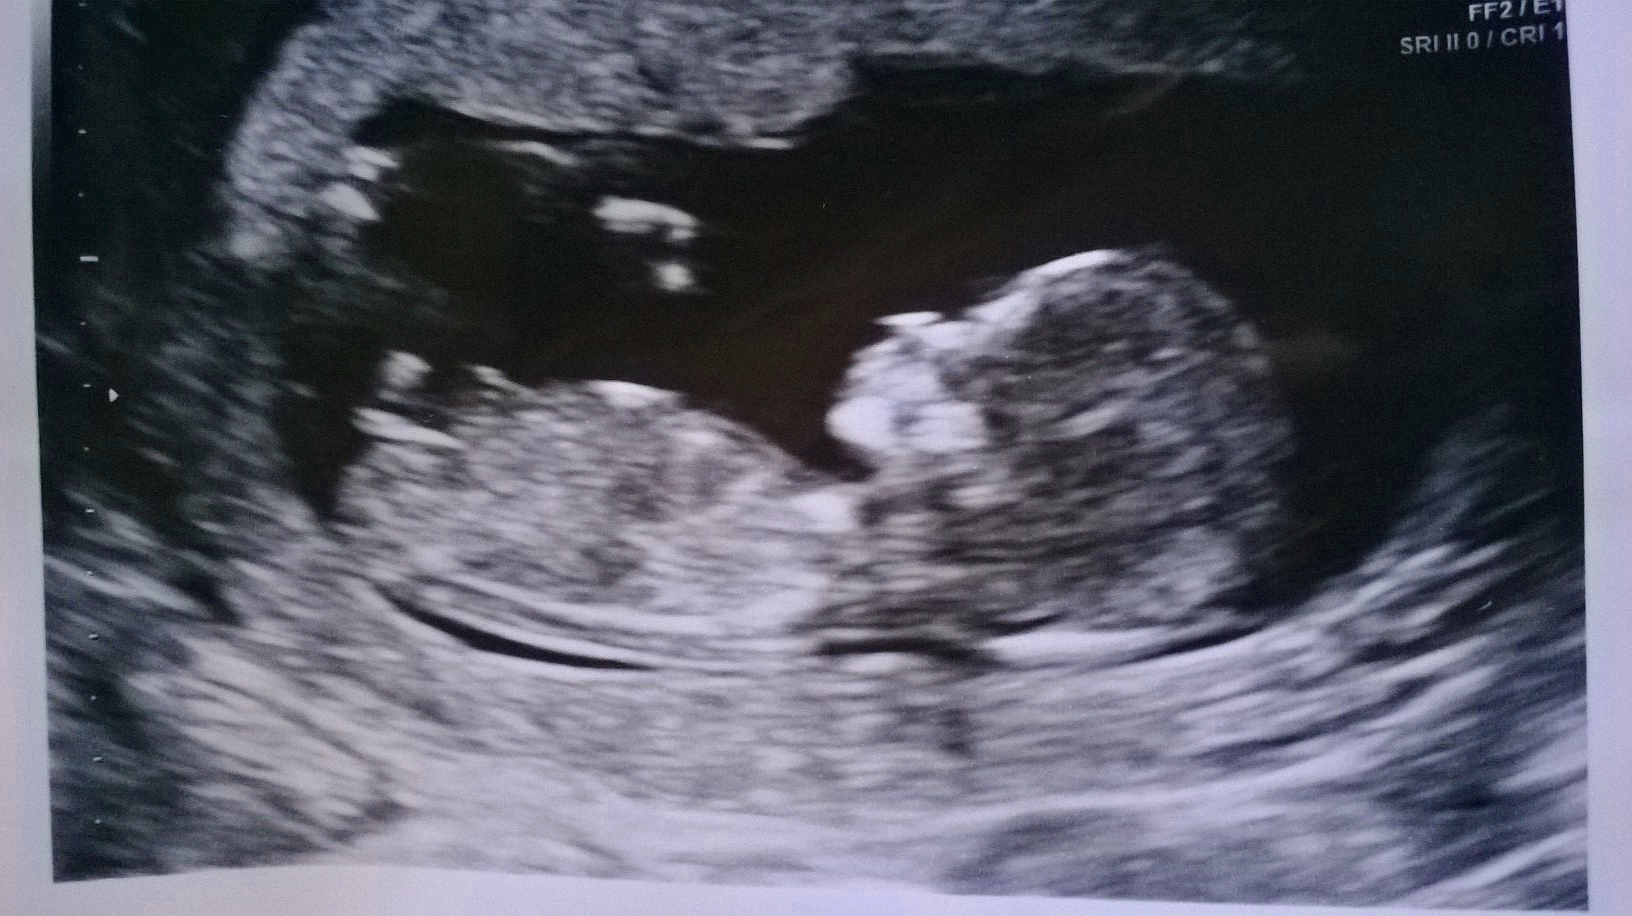

Boy or girl guesses please? : ) 14 weeks pic

Hey, very curious as to whether my bean is a boy or a girl! I've been recommended In-gender for good guesses so does anyone want to guess boy or girl from my latest scan pic, please? This was from a private scan done at 14 weeks. On the moving image/screen I definitely saw a 'spanner' shape thing/nub, which I've heard can indicate girl. It's sort of there in the pic just not as clear as I saw it on the screen. Opinions very welcome. Thanks very much.